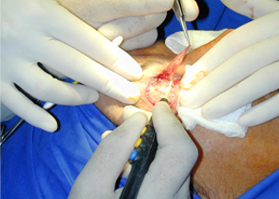

適用于細微、精細的切割如頭頸部,敏感部位皮膚的切割。

可實現(xiàn)切割,凝血同步。

適合于皮下組織的切割和剝離。

特別是在運血較為豐富的部位。